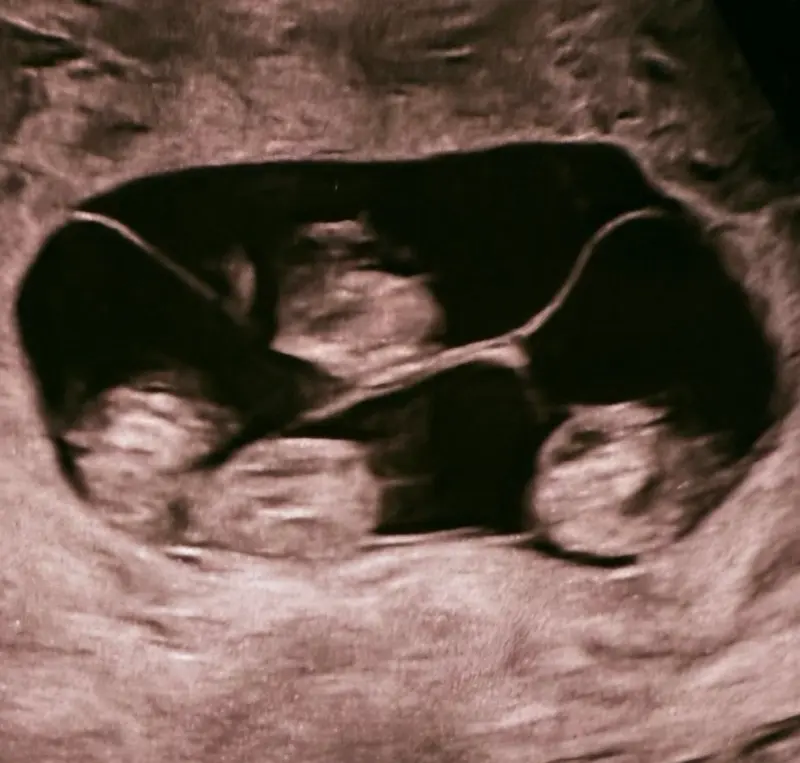

В одном из родильных домов Санкт-Петербурга случилось невероятное событие. Пациентка этого медучреждения произвела на свет сразу четырех младенцев женского пола, и все они являются монозиготными близнецами. Подобные ситуации ранее в нашей стране официально не фиксировались.

Как пояснил Евгений Михайлин, заместитель главврача и профессор, консультировавший роженицу, вероятность появления на свет монохориальной, то есть однояйцевой, четверни составляет примерно один случай на 15,5 миллиона родов. Масса тела новорожденных варьировалась от 1360 до 1640 граммов, а их рост — от 37 до 41 сантиметра. Медики отмечают, что для срока в 32 недели при многоплодной беременности это отличные параметры.

Согласно медицинской статистике, во всем мире зафиксировано лишь около 15 случаев рождения четверни-близнецов, причем в десяти из них на свет появились девочки.